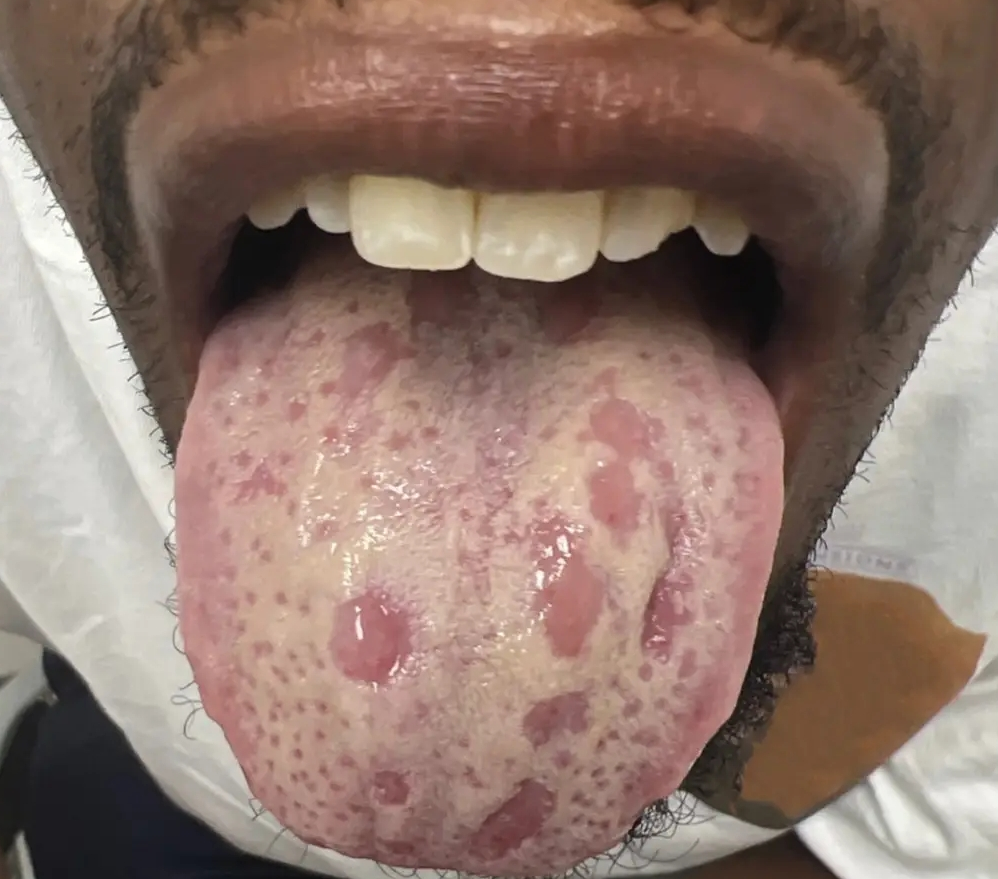

There are times you notice your gum begins to swell just like the picture above.

This can happen to both young people and adult.

Gum swelling is very painful and the pain can even lead to constant headache or migraine.

With our products, the swelling will go down within few days.